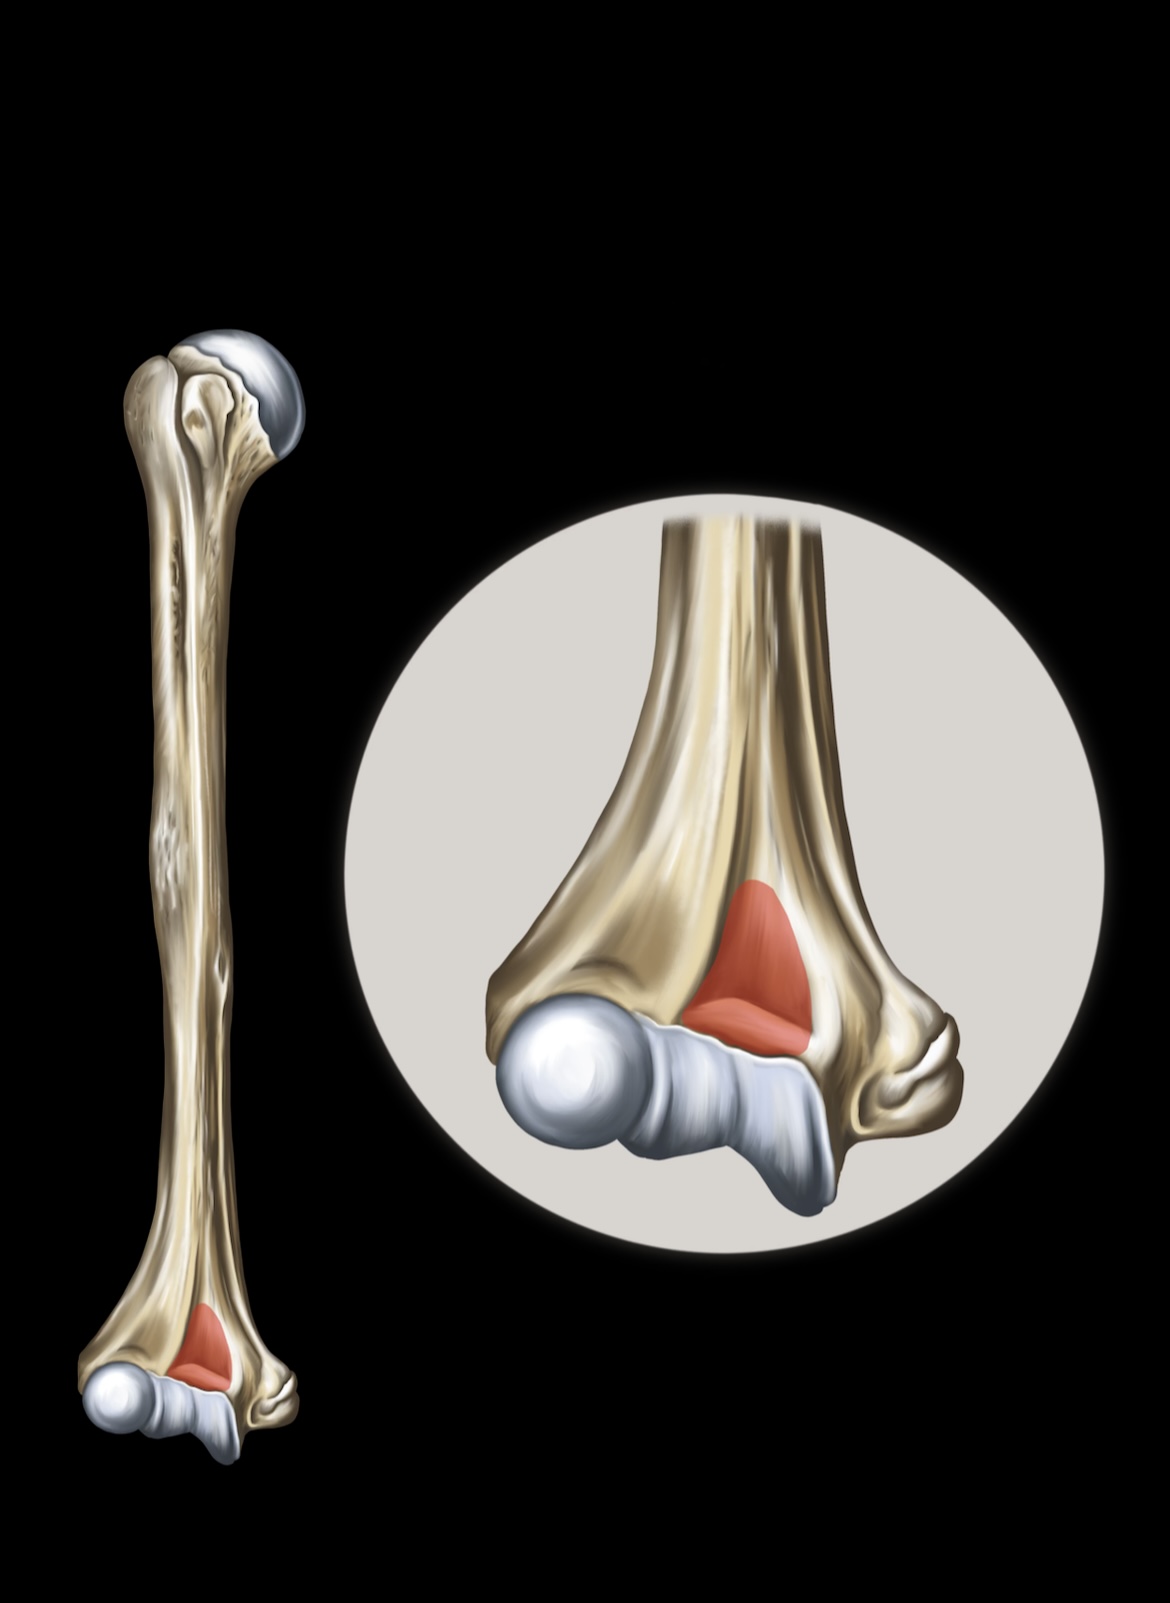

Humerus

Lateral Epicondyles of the Humerus

Medial Epicondyles of the Humerus

Ulna

Olecranon

Trochlear Notch

Ulnar Head